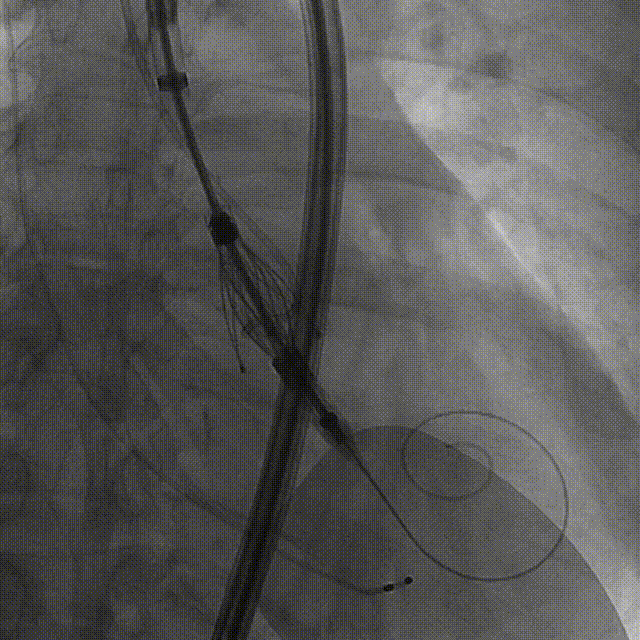

手术过程:5A 标准化流程SOP

术前右窦中心造影

大鞘植入

瓣膜对齐MARK

瓣膜调弯解离

瓣膜锚定键体位确认

瓣膜入窦

左窦确认

深度推进确认

起搏一键释放

术后造影